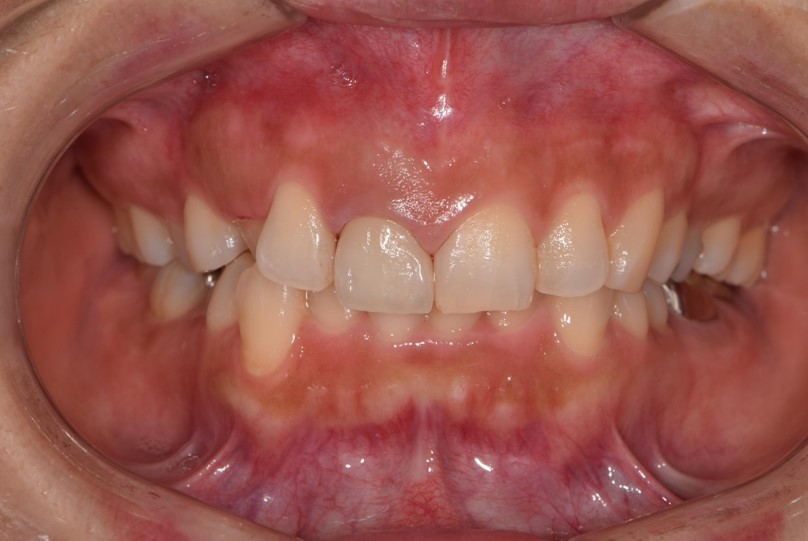

歯の色調がどうしても出せない場合、褪せてしまった歯を透明感のある歯に被せ物でよみがえらせる処置があります。